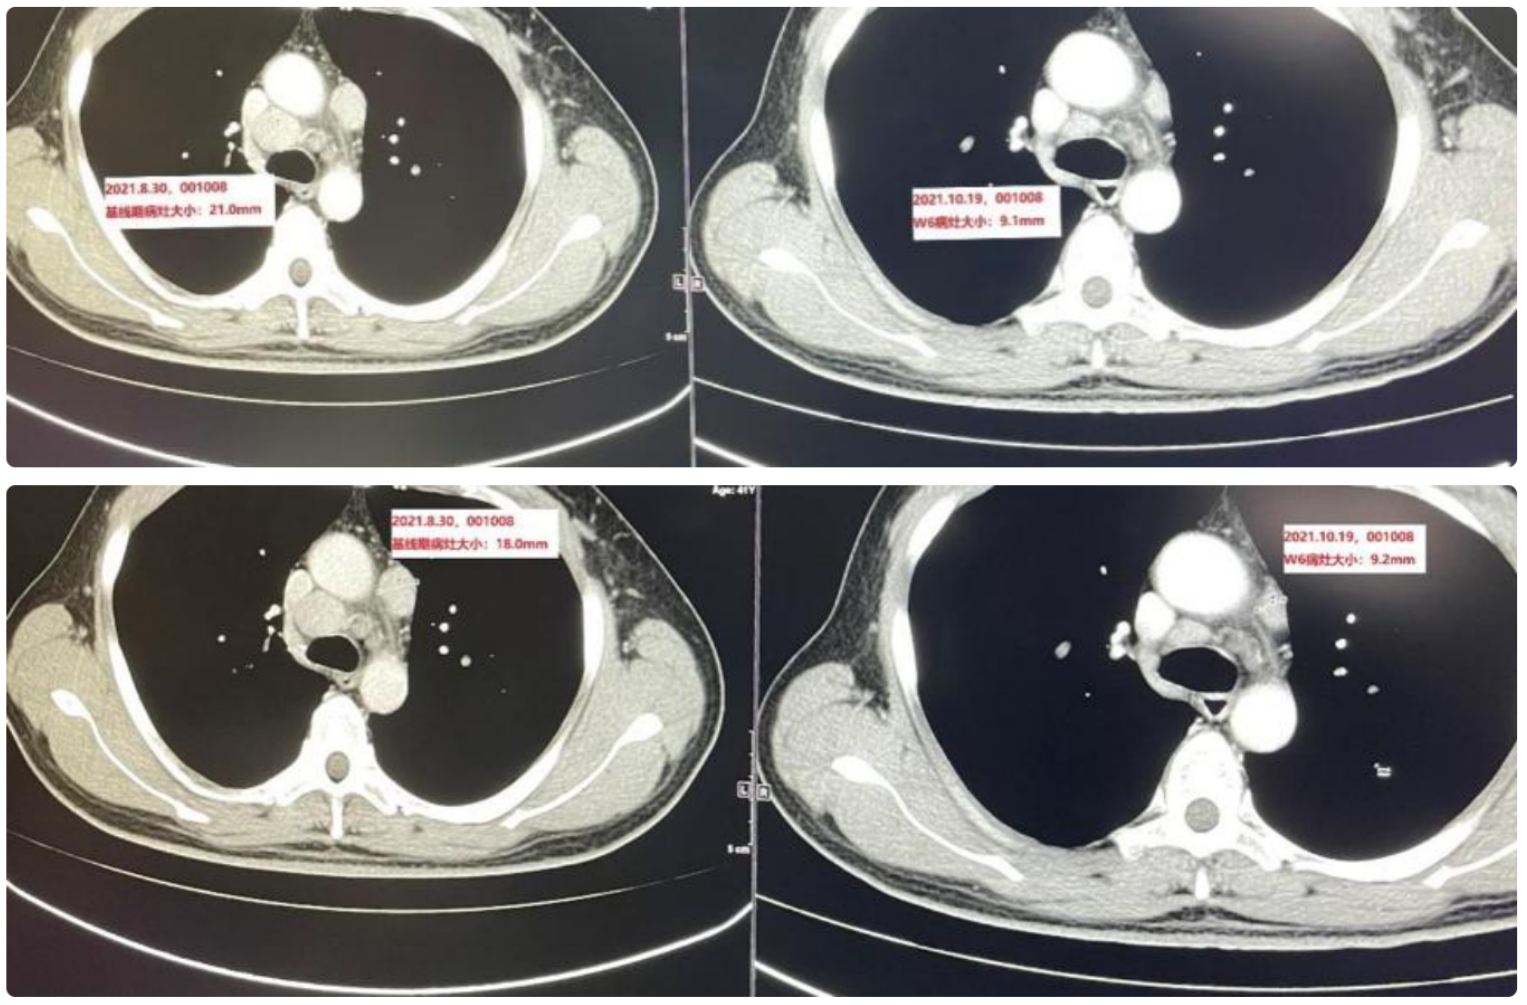

維貝柯妥塔單抗的“縮瘤”能力非常強(qiáng),基于獨(dú)特的“生物導(dǎo) 彈”設(shè)計(jì)(高親和力抗體、可裂解Linker和強(qiáng)效Payload殺傷),維貝柯妥塔單抗的療效已在后線鼻咽癌和頭頸鱗癌得到驗(yàn)證:以一位治療線數(shù)為4的轉(zhuǎn)移晚期鼻咽癌患者為例,僅入組維貝柯妥塔單抗的II期臨床試驗(yàn)并接受維貝柯妥塔單抗治療僅2次(6周),靶病灶直徑總和縮小53.1%,療效評(píng)估PR。

(左為治療前,右為治療后)